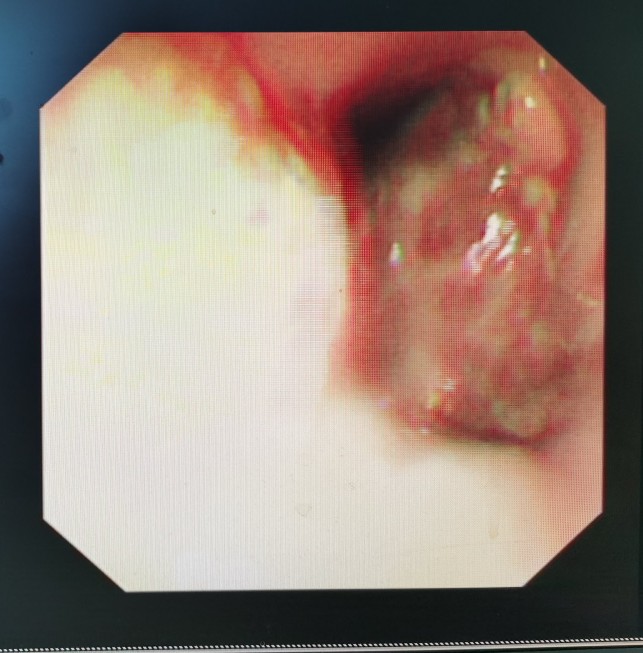

胃镜下看到的贲门肿瘤

从食管向胃方向看到的贲门肿瘤

贲门肿瘤已经快完全堵塞食管了